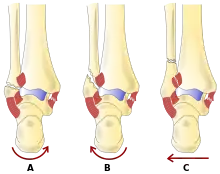

La région de la cheville fait référence à l'endroit où la jambe rencontre le pied (région talocrurale)[4]. L'articulation de la cheville est une articulation charnière complexe et fortement contrainte composée de trois os : le tibia, le péroné et le talus[5],[6]. L'aspect porteur du tibia le plus proche du pied (appelé plafond) se connecte avec le talus. Cette articulation (où deux os se rencontrent) est principalement responsable de la flexion plantaire (déplacer le pied vers le bas) et de la dorsiflexion (déplacer le pied vers le haut)[6]. Ensembles, le tibia et le péroné forment une douille en forme de support connue sous le nom de mortaise, dans laquelle s'insère le talus en forme de dôme[7]. Le talus et le péroné sont reliés par un groupe solide de ligaments, qui soutiennent la face latérale de la cheville. Ces ligaments comprennent le ligament talo-fibulaire antérieur (ATFL) et le ligament talo-fibulaire postérieur (PTFL)[8]. Le ligament calcanéo-fibulaire (LFC), qui relie le péroné au calcanéum, ou os du talon, fournit également un soutien latéral. Le ligament deltoïde soutient la partie médiale de la cheville (la plus proche de la ligne médiane). Il empêche le pied de s'éverser excessivement ou de se tourner vers l'extérieur, tout en empêchant également le talus de tourner vers l'extérieur[8]. Les parties distales du tibia et du péroné sont reliées par un réseau de tissu conjonctif appelé syndesmose, composée de quatre ligaments et de la membrane interosseuse[8].